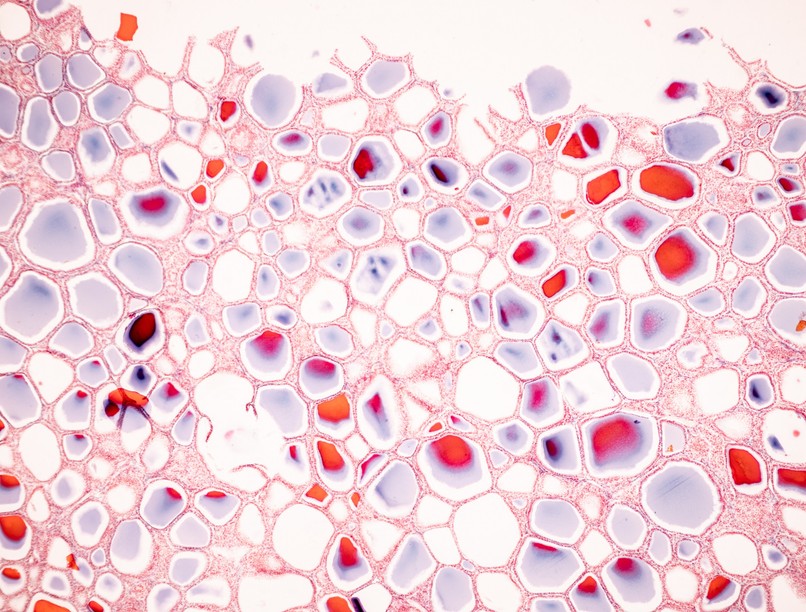

A hormonok a szervezet belső kommunikációs rendszerének kulcsfontosságú elemei. Ezek az anyagok kémiai hírvivőként működnek, és fontos szerepük van a test számos folyamatának szabályozásában. Az endokrin mirigyekben, például a pajzsmirigyben, mellékvesékben vagy az agyalapi mirigyben termelődnek, és a véráramba jutva elérik célsejtjeiket, amelyek reagálnak a hormonális üzenetekre.

A belső elválasztású, azaz endokrin mirigyekre jellemző, hogy nincs kivezetőcsövük, a váladékukat a vérbe juttatják, és azok a vér útján jutnak el a rájuk specifikusan érzékeny sejtekhez. Ezek a sejtek receptorokat tartalmaznak, amikhez a hormonok kapcsolódnak.

A hormonok, az endokrin mirigyek váladékai, speciális kémiai anyagok

Sok olyan hormonunk van, amely minden egyes sejtünkre hat, mint például az inzulin vagy a pajzsmirigyhormonok. De vannak olyanok is, mint például az FSH (follikulusstimuláló hormon) vagy az LH (luteinizáló hormon), amelyek specifikusan egy-egy területen fejtik ki a hatásukat.